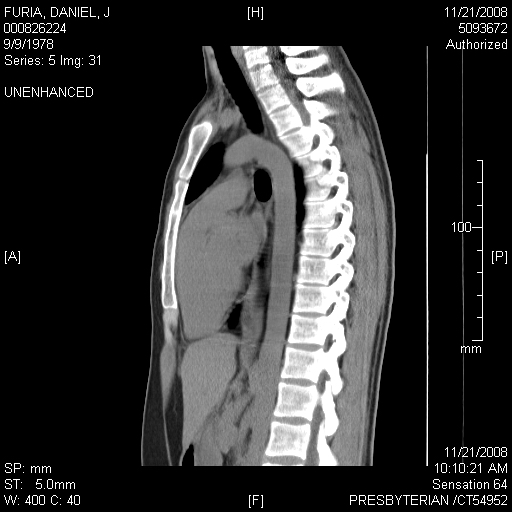

Some other CAT Scan Images I thought looked neat (healthy lung, not collapsed):